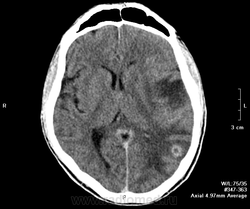

Мужчина, 40 лет. Поступил в тяжелом состоянии. В анамнезе туберкулез легких, на учете. Было высказано предположение и туберкуломах головного мозга. Нейрохирурги активно возражали, они были уверены, что это метастазы.

КТ с контрастом:

Через пару месяцев после противотуберкулезного лечения пришел на контроль на своих ногах и с его слов: "прекрасно себя чувствует". Контратировать не стали, т.к. с венами большие проблемы. Видно не без вредных привычек мужчина. Возможно появиться еще на контроль через несколько месяцев.